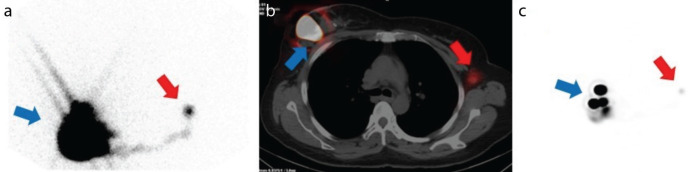

Results: A total of 16 patients were evaluated, with a median age of 56 years (range 30-73), all of whom were female. Lymphoscintigraphy successfully localized the SLN in 81.3% of the patients. In eight patients, the SLN was located in the ipsilateral axilla, while in five patients, it was found in the contralateral axilla. Axillary lymph node dissection (ALND) was performed in three patients (all in the contralateral axilla) due to metastatic involvement in the SLN. ALND during first surgery was associated with an increased likelihood of SLN detection in the contralateral axilla or Re-SLNB failure (p=0.043).

Conclusion: In patients undergoing surgery for IBTR, the likelihood of the SLN being in atypical locations is high. Lymphoscintigraphy may enhance the success of Re--SLNB in this patient group.